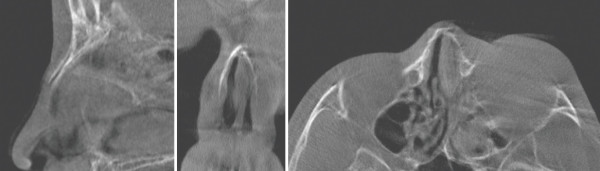

비골골절로 내원한 15세 남성 환자. 수상 후 5일이 경과한 모습. 수상에 의한 안와골절과 비골골절, 비중격 골절 등이 동반되었다. 정면 사진상 좌측 눈과 코 주변에 부종과 멍이 관찰된다. 측면 사진상 콧대에 안장코 변형, 밑면 사진상 비공의 비대칭을 확인할 수 있다

수술 전 CT scan. 좌측 안와 주변에 심한 부종이 관찰된다. 주로 좌측 비골골절과 비중격의 안장코 변형을 확인할 수 있다.